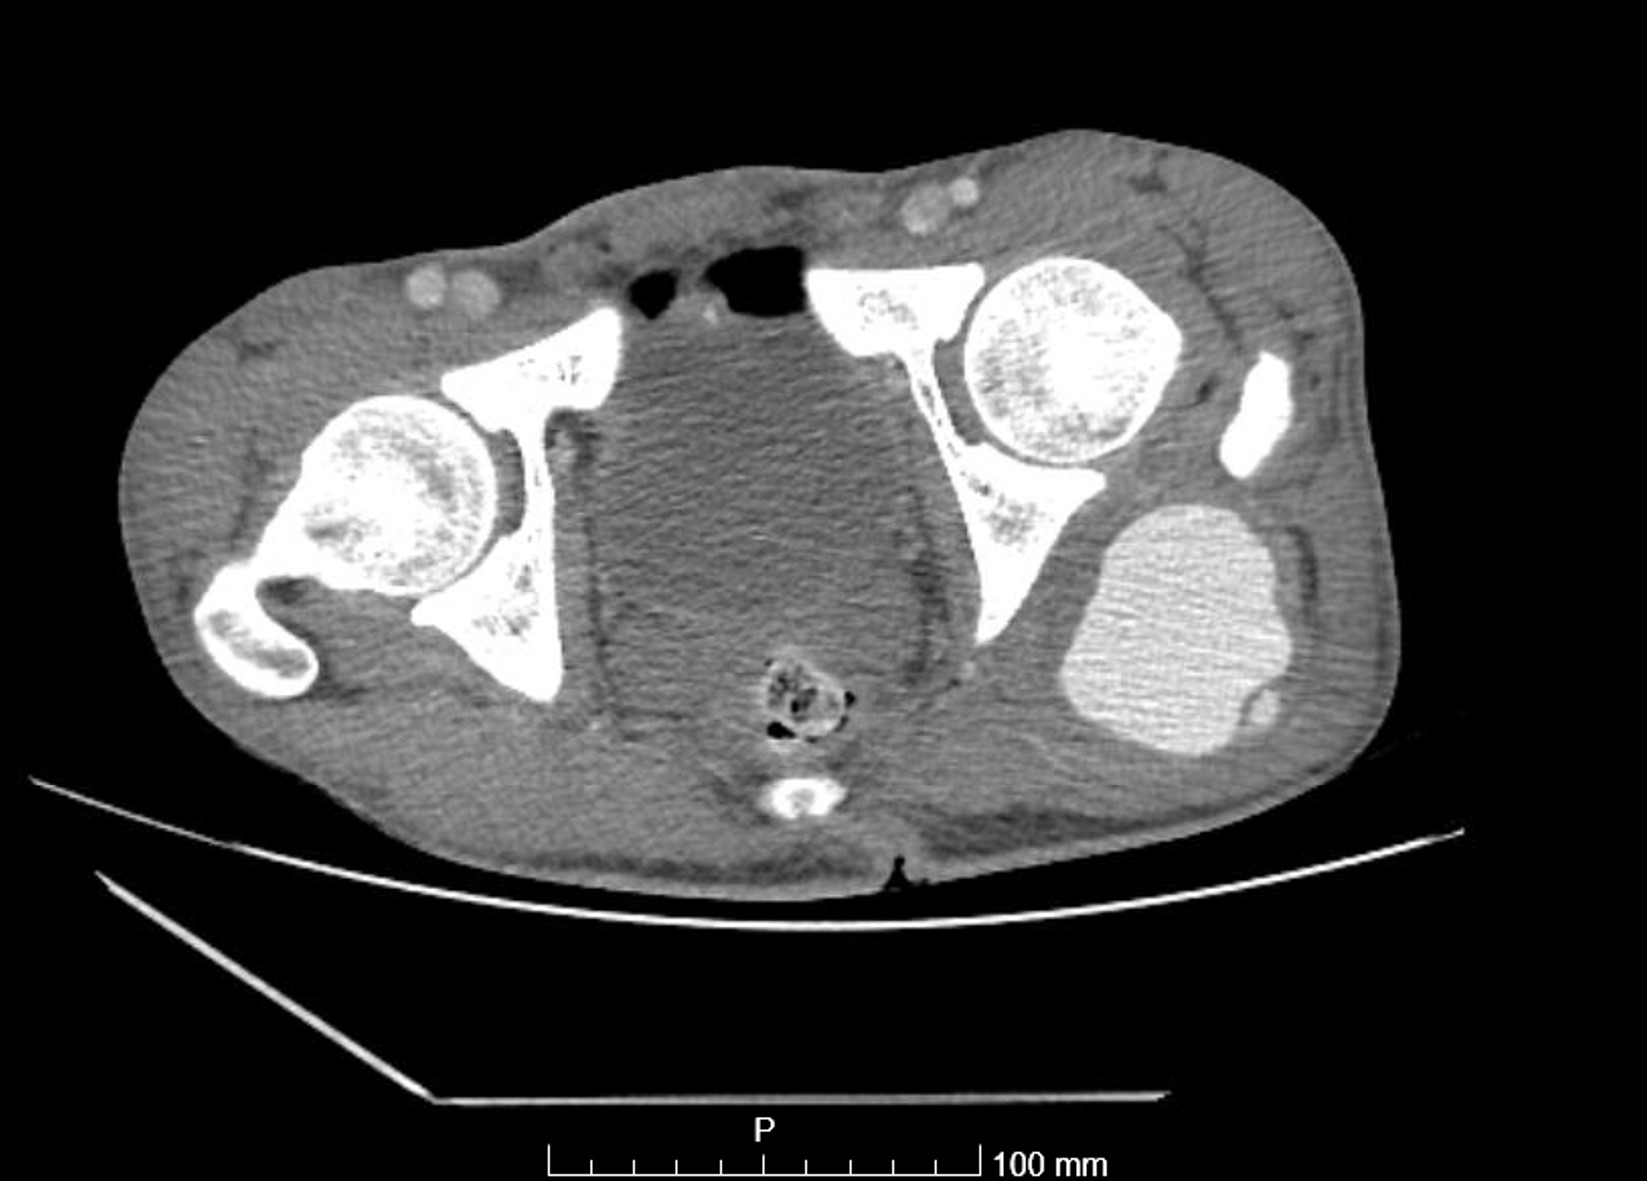

Pseudoaneurisma postraumático de arteria glútea izquierda.

Se pauta tratamiento analgésico y se deriva a servicio de radiología intervencionista de hospital de referencia para tratamiento endovascular. Resultando ser Pseudoaneurisma de arteria glútea anómala por arteria ciática persistente, se implanta stent cubierto excluyendo pseudoaneurisma.

El caso se evalúa en comité Vascular posteriormente decidiendo mantener anatomía anómala del paciente ante resultado favorable. El paciente se encuentra estable, con pulsos positivos, es trasladado nuevamente a nuestro hospital para continuar tratamiento rehabilitador.